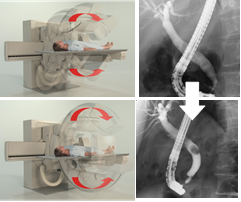

C臂旋轉(zhuǎn)多角度觀察

在內(nèi)徑與膽管、腸氣等結(jié)構(gòu)圖像重疊時(shí),只需旋轉(zhuǎn)C臂即可將重疊的影像分開觀察,避免讓患者翻身造成內(nèi)徑脫落的風(fēng)險(xiǎn)。